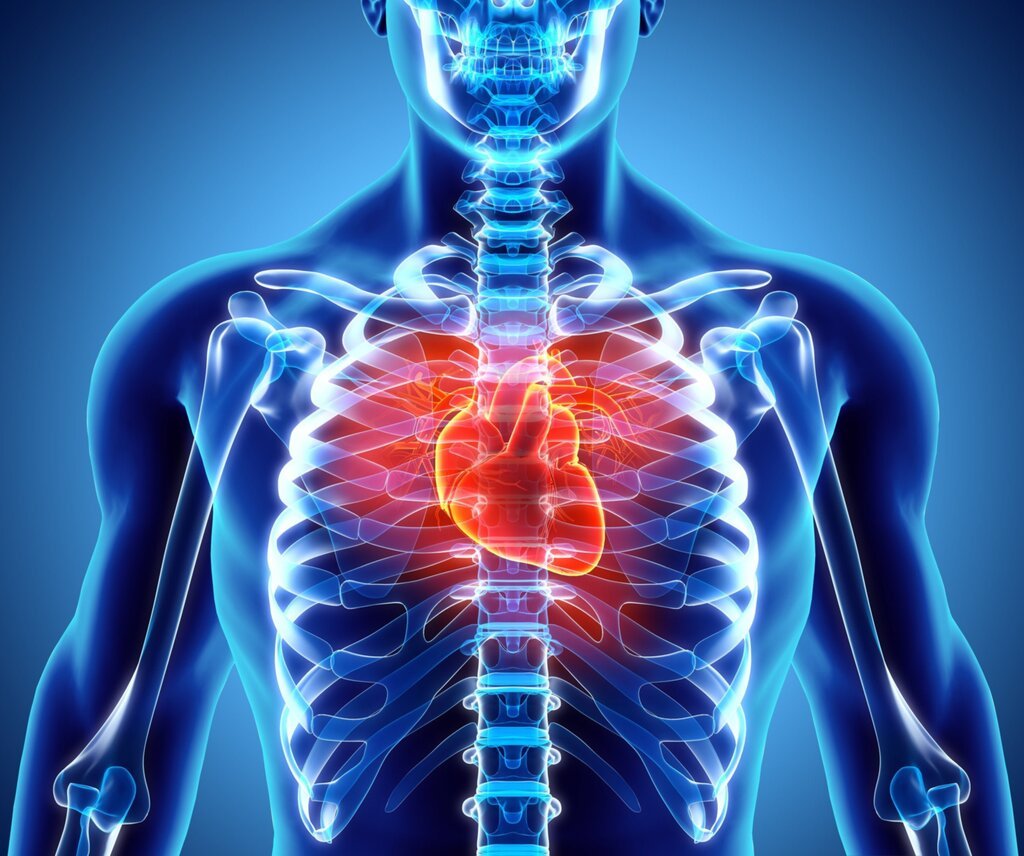

Bu kalp sana yeter mi? Her zaman değil…

Nefes almakta zorlanıyor, kısa mesafe yürüyüşlerde bile kolayca yoruluyorsanız nedeni kalp yetmezliği olabilir. Geceleri uykunuzdan uyandıran ve çarpıntılarla kendini gösteren kalp yetmezliğinin ömrünüzü kısaltmasını engellemek sizin elinizde. Özellikle ailesinde kalp yetmezliği olan kişilerin kalp yetmezliği riskiyle karşılaşma olasılığının daha fazla olduğuna dikkat çeken Avrasya Hastanesi Başhekimi Prof. Dr. Ali Rıza Cenal, kalp yetmezliği ile ilgili önemli bilgiler veriyor.

KALP YETMEZLİĞİ NEDİR?

Kalpteki daralmış arterler veya tansiyon gibi etkenler kalbin yorulmasına neden olur. Bazı durumlarda enfeksiyon nedeniyle de kalp yetmezliği gelişir. Kalp yetmezliği düşük tansiyon halsizlik, ödem, kilo alma ve nefes darlığıyla ortaya çıkar. Hastalığa sebep olan her etkeni ortadan kaldırmak mümkün olmayabilir. Ancak belirtiler tedavi ile iyileştirilebilir ve yaşam standardı yükseltilebilir.

HASTALIĞI TETİKLEYEN ETKENLER VAR…

Genellikle kalp kasının zarar görmesiyle ortaya çıkan kalp yetmezliği yaşlanmayla birlikte yüksek risk taşımaya başlar. Hastalığın ortaya çıkmasında rol oynayan başlıca etkenler şu şekildedir;

- Hipertansiyon: Kan basıncının kontrolsüz bir şekilde yükselmesiyle kalbin yapısı bozulur ve buna bağlı olarak kalp yetmezliği ortaya çıkar.

- Kalp kapak hastalıkları: Kalp kapakçıklarının olması gerektiği gibi açılıp kapanmaması sonucunda meydana gelir.

- Kalp krizi: Kalp damar tıkanması sonucunda kalp krizi gelişir, kalp kasına yeterince oksijen sağlayamaz ve kalp kasında hücreler ölür.

- Yaşlanma: Kalp yetmezliği genel olarak 35 yaş üzeri kişilerde görülmektedir. Yaşlanmaya bağlı olarak kalbin kasılma ve kan pompalama yeteneği azalır ve kalp yetmezliğini ortaya çıkarır.

BELİRTİLERİ GÖZ ARDI ETMEYİN!

Kalp yetmezliği hem kronik hem de aniden gelişen yani akut bir hastalıktır. Özellikle nefes darlığı ve tıkanmayla kendini hissettirir. Bunun yanında;

- Çabuk yorulma,

- Göğüs ağrısı ve çarpıntı,

- Yüksek yastıkta uyuma ihtiyacı,

- Kesik kesik nefes alma,

- Bacak ve ayaklarda şişlik,

- Kilo alma,

- Halsizlik ve yorgunluk,

- Öksürük,

- Nefes alırken zorlanma,

- Hızlı kalp atışı gibi semptomlar kalp yetmezliğinin belirtileri arasındadır.

TEŞHİS VE TEDAVİDE NASIL BİR YOL İZLENİR?

Kalp yetmezliğinin teşhisinde öncelikle hastanın şikayetleri ve hikayesi dinlenir. Sonrasında fiziki muayene yapılarak bazı testler uygulanması istenir. Kan tahlili, EKG, göğüs röntgeni, stres testi, ekokardiyogram gibi testlerle hastalık teşhis edilir. Sonrasında ise uygun tedaviye başlanır.

Kalp yetmezliğinin tedavisinde iki önemli amaç vardır. Birincisi nedeninin ortadan kaldırarak hastadaki belirtileri azaltmak ve hastanın rahatlamasını sağlamak, ikincisi ise hastanın ölüm riskini ortadan kaldırarak yaşam süresini uzatmaktır. Muayene sonrası hasta için uygun bir tedavi yöntemi belirlenir. Hastalığın nedenine ve seviyesine göre damar genişletici ve kan sulandırıcı ilaçlara başvurulabilir. İlaçlar hastalığın aşamasına göre değişiklik gösterebilir. İlaç tedavisinin yeterli olmadığı durumlarda ise uygulanacak tedaviler şu şekildedir;

- Kalp pili: Kalp pompalama gücünün ileri derecede azalması gibi durumlarda kalbin düzenli çalışması amacıyla kalp pili yerleştirilmesi ameliyatı uygulanabilir.

- Bypass: Koroner arterde meydana gelen daralma nedeniyle kalp krizi riski ortaya çıkmaktadır. Böyle durumlarda tıkanıklık, daralma ve kalp krizi riskini önlemek amacıyla koroner stentbypass operasyonuna başvurulur.

- Kalp nakli: Mevcut tedavi yöntemleriyle iyileşme sağlanmaması ve hastalığın çok ilerlemesi durumunda kalp nakli gerekir. Kalp nakli sonrası belirtiler minimuma iner.

HASTALAR İÇİN BESLENME ÖNERİLERİ

Kalp yetmezliği olan hastaların beslenme şekline dikkat etmesi yaşam kalitesinin yükseltilmesi açısından oldukça önemlidir. Hastalar öncelikle tuz kullanımını sınırlandırmalı, meyve, sebze tüketimine ağırlık verilmeli, tahıl ve balık gibi besin değeri yüksek yiyecekleri öğünlerine dahil etmelidir. Kayısı, muz, portakal gibi potasyum değeri yüksek meyvelerle vücudun ihtiyacı olan potasyum miktarı, yağlı tohum ve sebzelerle ise magnezyum ihtiyacı karşılanmalıdır. Hastalar günde 1,5-2 litre arası sıvı tüketilmeli, alkolden ve sigaradan uzak durmalıdır.